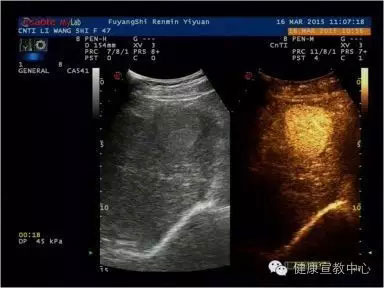

(甲乳分級診斷彈性評估技術(shù))

目前,科室開展的聲學(xué)造影已廣泛應(yīng)用到肝臟、膽囊、胰腺、腎臟、脾臟、子宮、甲狀腺、乳腺、淋巴結(jié)等,特別是在乳腺癌診斷尤其是早期病變甚至是癌前期病變的診斷中均取得突破性進(jìn)展。超聲造影、彈性成像及超聲甲、乳結(jié)節(jié)綜合分類法均為2014年在皖北率先相繼開展的新技術(shù),兩年多以來共開展造影500多例,200多名患者從中受益。隨著我院南區(qū)的全面開診,甲、乳診療中心及其他超聲學(xué)科聯(lián)合體的創(chuàng)立、高端機(jī)器設(shè)備的添置,聲學(xué)造影、彈性成像等新技術(shù)會(huì)拓展到其他學(xué)科,如生殖中心、婦科及外傷性病變等等。

(超聲造影輔助分類)